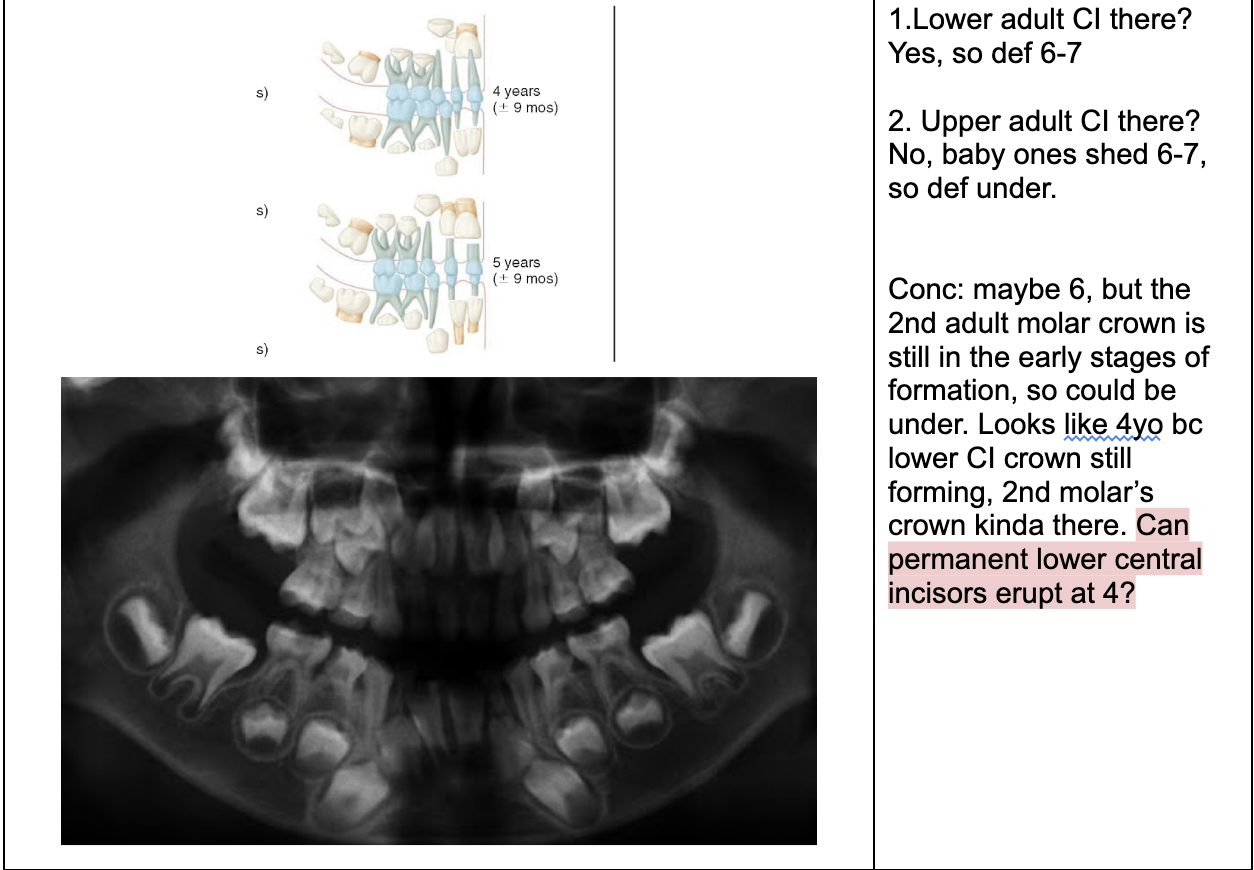

1.lower adult CI there? YES, so def 6-7

1. Upper Ad. Ci there? NO, so either 6-7 or under

Last molar crown not really formed so 6?

NOTE- THE 8’s - crown starts developing at 9 yo.